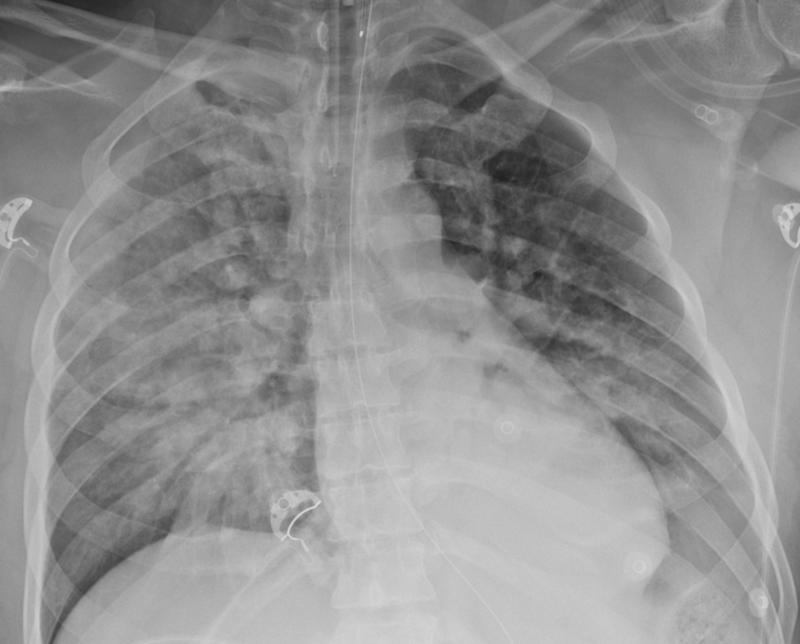

Gallery Pneumonia Aspiration (hanging)

Aspiration (hanging)